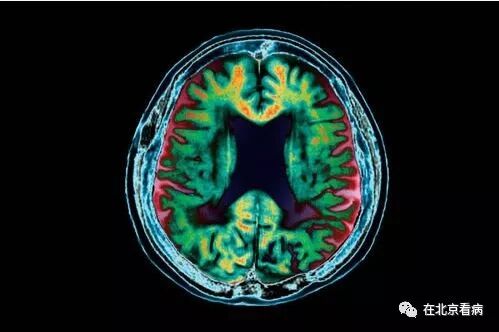

阿尔茨海默氏症蛋白能在共享血液供给的小鼠间扩散并导致大脑退化。

你是否会患上阿尔茨海默氏症?关于该疾病或许能通过输血和手术设备扩散的恐惧一直在增长,但很难找到这种情况正在发生的证据。如今,一项发表于《分子精神病学》杂志的研究发现,一种阿尔茨海默氏症蛋白能在共享血液供给的小鼠间扩散并且导致大脑退化。

和CJD一样,阿尔茨海默氏症也涉及一种被称为β-淀粉样蛋白的错误折叠蛋白。这种蛋白斑块在患有该疾病的人类大脑中堆积,尽管目前尚不知道斑块是疾病的诱因,或者仅是一种症状。

有证据表明,β-淀粉样蛋白可能像朊病毒一样传播。如今,一项研究发现,当健康小鼠被同拥有阿尔茨海默氏症斑块的小鼠结合在一起时,前者最终开始在大脑中形成β-淀粉样蛋白斑块。当斑块以这种方式在健康小鼠体内形成,它们的大脑组织随后开始坏死。

这表明,阿尔茨海默氏症确实能通过血液中的β-淀粉样蛋白传播。“这种蛋白能进入同患病小鼠相连的健康小鼠的大脑并且导致大脑退化。”领导此项研究的加拿大英属哥伦比亚大学科学家Weihong Song表示。

β-淀粉样蛋白开始在健康小鼠的大脑内堆积。在4个月的时间里,小鼠大脑中负责学习和记忆的关键区域的活动模式也发生了改变。Song表示,这是科学家首次发现β-淀粉样蛋白会进入另一只小鼠的血液和大脑并且引发阿尔茨海默氏症的症状。